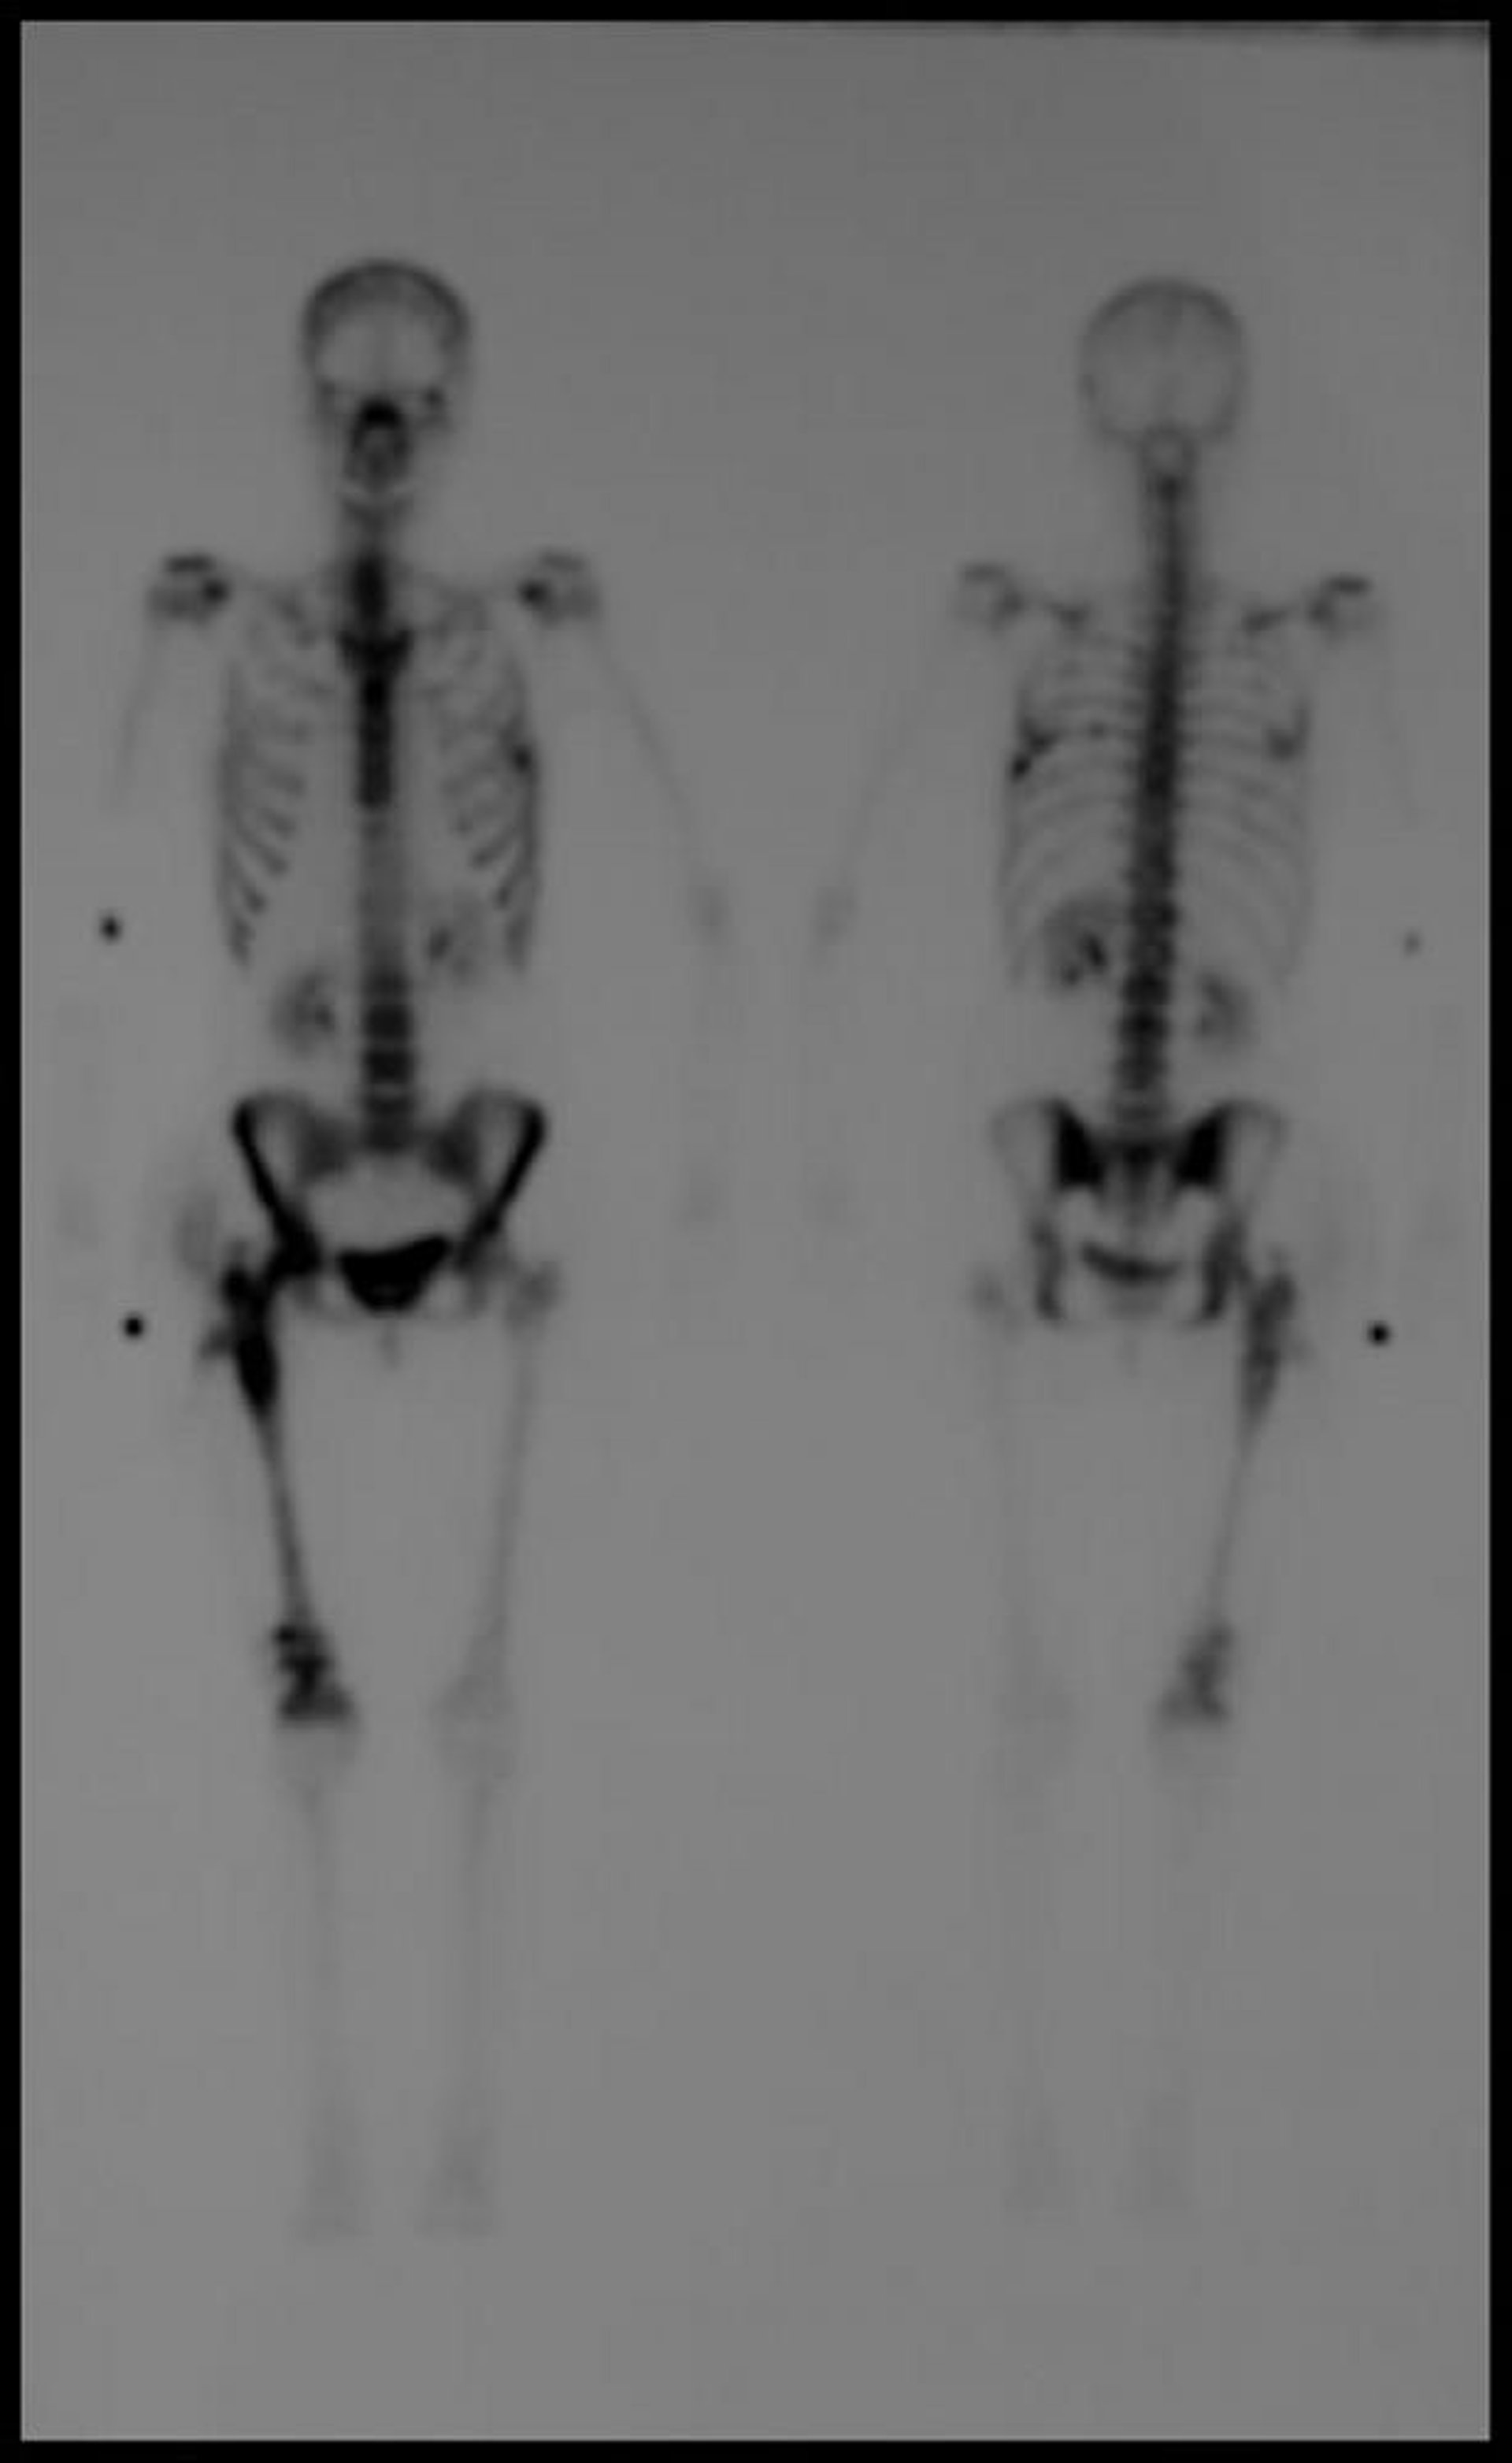

全身の骨シンチグラフィー

テクネチウム99mによる全身の骨シンチグラフィーの遅延像では,転移病変に一致する複数の取り込み部位が認められる。

Image courtesy of Hakan Ilaslan, MD.